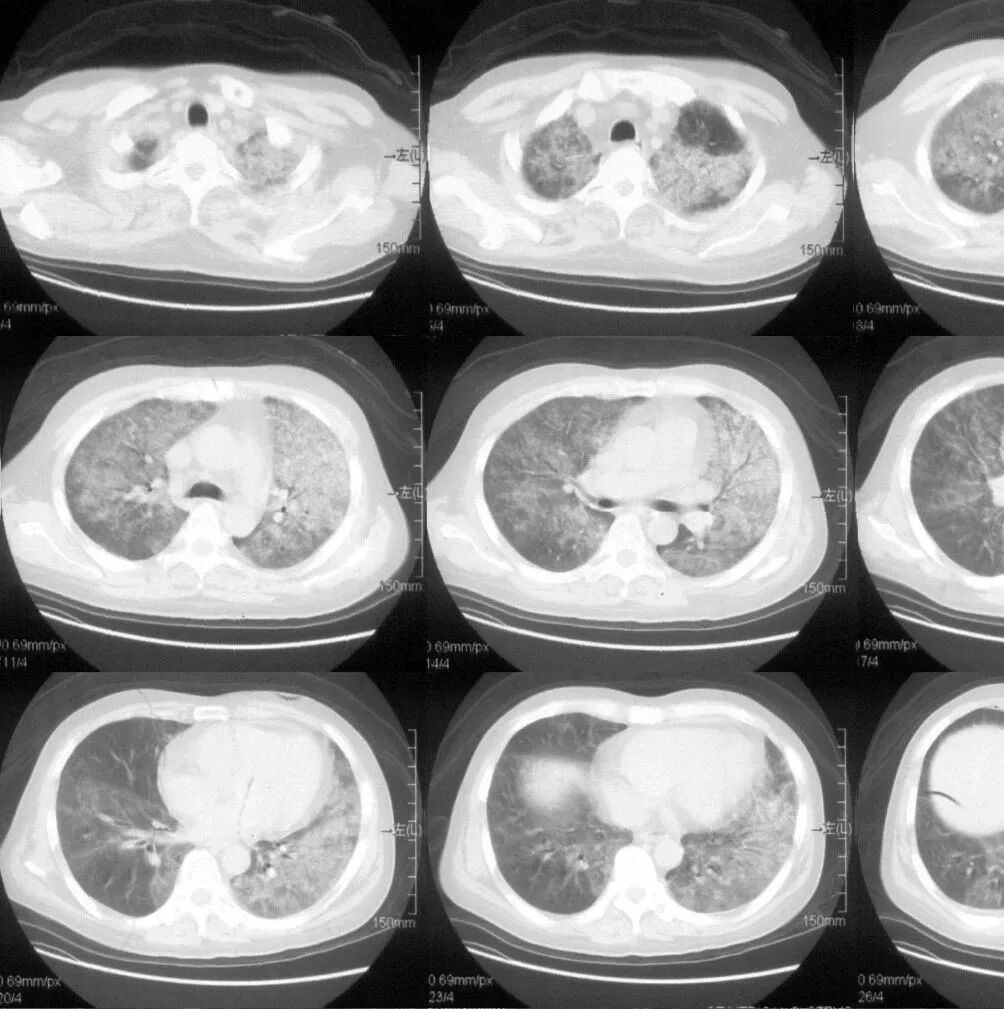

CT即电子计算机断层扫描,它是利用精确准直的X线束、γ射线、超声波等,与灵敏度极高的探测器一同围绕人体的某一部位作一个接一个的断面扫描,供完整的三维信息,具有扫描时间快,图像清晰等特点,可用于多种疾病的检查。

CT的辐射剂量相较于X光片大一点,普通健康体检检查尽量选择低剂量CT筛查而不是常规CT,怀孕妇女不宜进行CT检查。

肺部CT 检查

1、普通平扫

即常规的CT检查,一般只需要躺在CT机上面进行扫描便可,无需打造影剂,速度快,方便简洁,故常作为初次检查、急性病变的首要检查方案。

2、增强扫描

在平扫CT的基础上,静脉注射造影剂(常用碘对比剂),通过血液循环跑到全身组织器官中,相当于给平扫的CT润色一番,有助于更加准确地分辨血液循环丰富的器官组织病变,如肿瘤。

一般来说,如果普通平扫CT能看清楚病变,并能做出明确的影像学诊断,那就不需要进一步做增强CT了,否则,需要完善增强CT以明确诊断。

胸部 肺、胸膜及纵膈各种肿瘤、肺结核、肺炎、支气管扩张、肺脓肿、囊肿、肺不张、气胸、骨折等;对于显示肺部病变有非常满意的效果,对肺部创伤、感染性病变、肿瘤等均匀有很高的诊断价值。对于纵隔内的肿物、淋巴结以及胸膜病变等的显示非常清晰也令人满意,可以显示肺内团块与纵隔关系等。